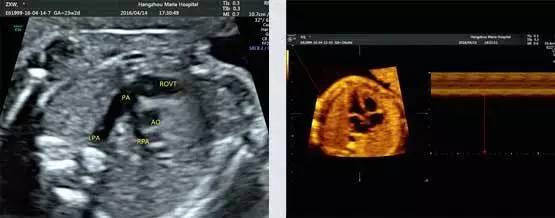

目前检查胎儿是否畸形,国际上最通用也是很安全的方式是超声检查。现在国际上这方面最普遍的仪器就是美国GE集团的GE Voluson E8四维彩超仪器,阳泉华康医院作为阳泉专业妇产医院,率先引进美国GE Voluson E8四维彩超设备,为母婴健康保驾护航。

美国GE Voluson E8对胎儿心脏、唇裂、四肢发育异常、脑膜膨出、脊柱裂、腹壁裂等先天性畸形及发育异常能达到最佳的检测效果,为临床诊断提供准确的科学依据。

胎儿常见畸形检查图

(脊柱裂)

(柠檬头)

(右侧缺指)

(左肾缺如)

(前脑无裂畸形,喙鼻)

(多发畸形)